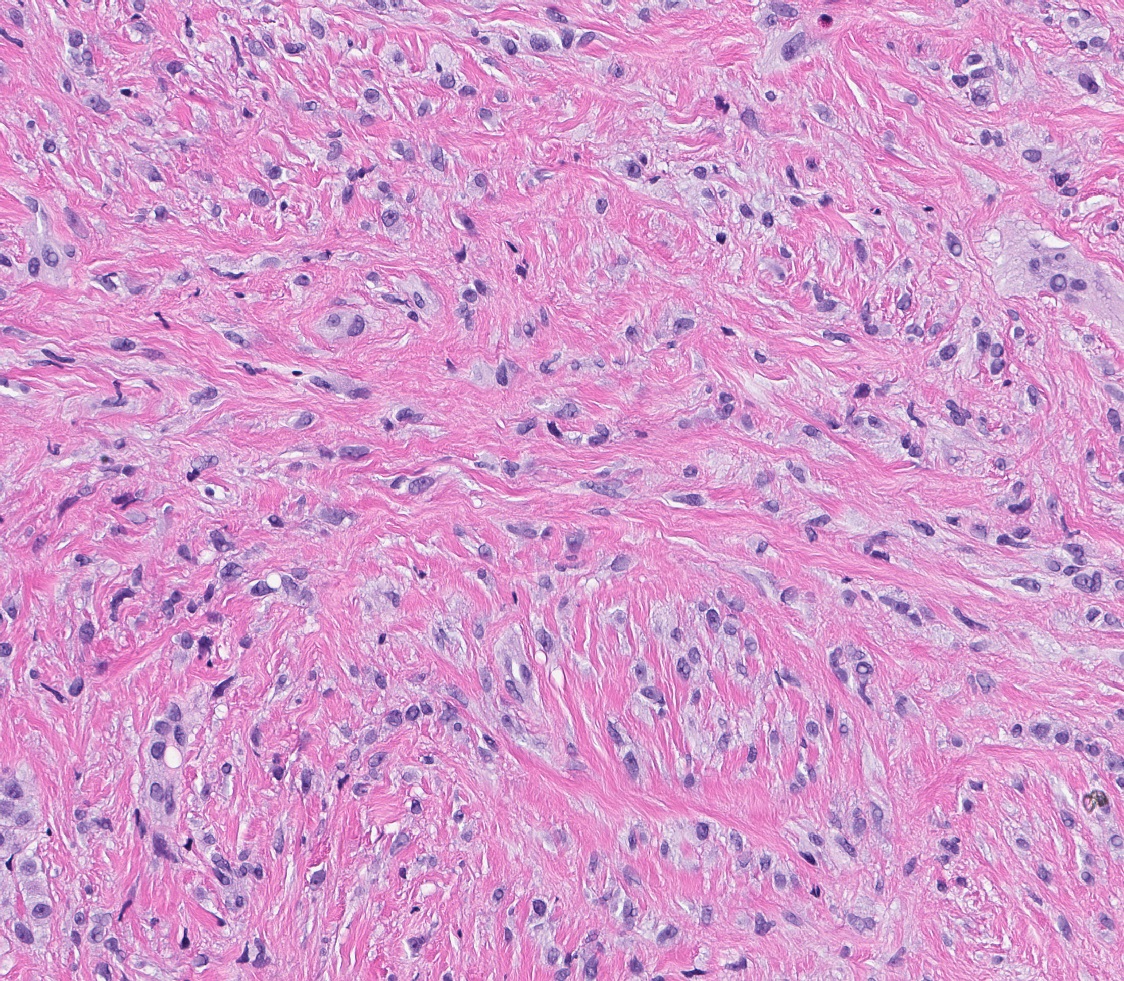

Microscopic (histologic) images

- Bland, uniform, short to elongated spindle cells arranged as short haphazard intersecting fascicles admixed with bands of hyalinized, brightly eosinophilic collagen and variable amounts of fat

- No more than mild nuclear atypia

- Mitoses usually absent, atypical mitoses and necrosis absent

- Mast cells common, perivascular lymphocytic infiltrates on occasion

- Focal myxoid stromal changes common

- Collagenized / fibrous: collagenous stroma predominates, may have hypocellular myofibroblastic spindle cell component